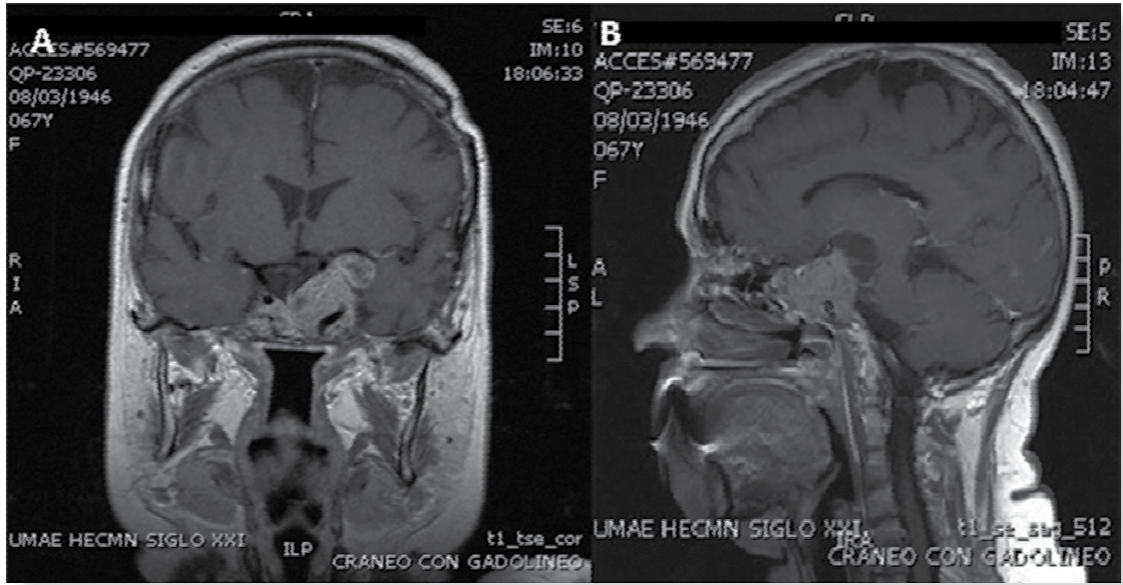

Se trata de una mujer de 53 años de edad, sin antecedentes heredofamiliares ni personales patológicos de importancia para el padecimiento actual, quien acudió a valoración endocrinológica por padecimiento de un año y medio de evolución caracterizado por hemianopsia bitemporal y disminución de la agudeza visual con predominio en ojo izquierdo, progresiva, acompañada de cefalea, sensación de cuerpo extraño, lagrimeo, fotofobia y miodesopsias. Debido a esta sintomatologia se realizó tomografia computada de cráneo donde se hizo evidente una lesión en la región selar de 35 X 30 X 35 mm con invasión al seno cavernoso izquierdo, desplazamiento del infundíbulo y compresión del quiasma óptico (Figura 1). La evaluación endocrinológica inicial no mostró evidencia bioquímica de hipersecreción hormonal y se concluyó que se trataba de un adenoma de hipófisis no funcional (Tabla 1). Se operó ese mismo año mediante un abordaje transesfenoidal con una reducción tumoral de 80% y recuperación parcial del campo visual; permaneció con hipopi-tuitarismo a expensas de hiposomatotropismo, hipogonadismo hipogonadotrópico, hipocortisolismo e hipotiroidismo central, estos últimos sustituidos con levotiroxina y prednisona vía oral.

Figura 1 Resonancia magnética nuclear de encéfalo con gadolineo en t1 en cortes sagital (a) y coronal (b) previo al inicio de tratamiento con temozolamida.

Al evaluar la RMN un año después del inicio del tratamiento combinado con análogos de la somatostatina y agonista dopaminérgico, se encontró una reducción tumoral de 20% en comparación con el estudio previo. A pesar de ello, 12 meses después se documentó recrecimiento tumoral del remanente (Figura 1), por lo que se decidió enviarla a tratamiento oncológico con temozolamide 150 mg/m2 durante 6 ciclos; evolucionó con estabilidad tumoral y se continuó con la vigilancia con RMN de hipófisis semestral (Figura 1); clínicamente, ha evolucionado sin cefalea, con persistencia de déficit campimétrico, pero que no ha empeorado.